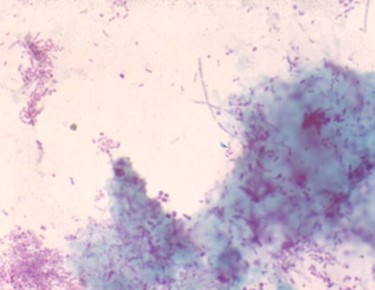

A PA of the chest shows a right hilar mass lesion and a miliary infiltrate. A modified acid fast stain of an aspirate from one of the skin lesions is shown below (see panels 2 & 3 below).

Nocardia asteroides is an opportunistic aerobic bacterium of higher order whose physical characteristics resemble those of actinomyces - a strictly anaerobic organism. Both species are Gram positive branching beaded coccobacilli, whereas nocardia is also modified acid fast positive (see right panel above). There are over a hundred nocardia species, many of which are implicated in human disease. Nocardia is a ubiquitous soil organism involved in the decay of organic materials.Nocardia usually gains entry through the lungs where it is characterized by its ability to cause a subacute pneumonia and to mimic miliary and cavitary tuberculosis and tumor (see middle panel above). In the host, with defective cell-mediated immunity, dissemination to the brain (most common), skin (see left panel above), and internal organs, may occur. In addition to his skin and pulmonary involvement, the presented case had nocardia endocarditis and a one liter abdominal wall nocardia abscess. Trimethoprim (10-20 mg/kg)-sulfamethoxazole (50-100 mg/kg) (TMZ-SMX) given in two divided doses per day is the drug of choice in most cases of nocardia infection. Daily doses TMZ-SMX doses can be reduced to as little as 5/25 mg/kg after induction therapy. For immunocompromised hosts and for those who are immunologicaly competent with brain abscesses, treatment should continue for 12 months. Pulmonary involvement in normal hosts requires 6-12 months of treatment. Unfortunately, the presented case expired despite the introduction of parenteral treatment with TMZ-SMX.